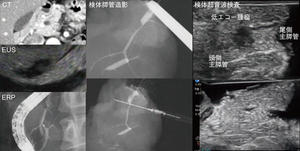

図1 標本造影/超音波検査を行った症例

〈講演1〉より正確な診断を目指した画像と病理の対比

池田恵理子(自治医科大学内科学講座消化器内科学部門・病理診断部)